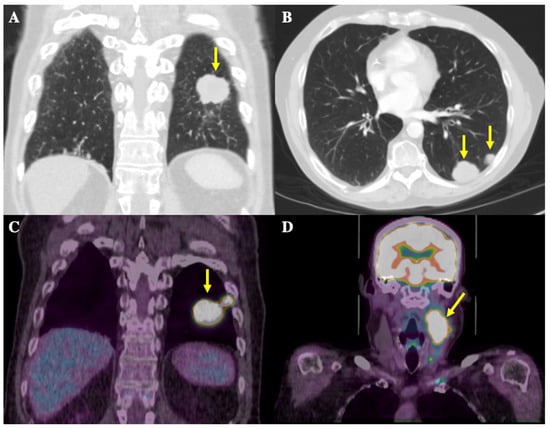

In the summer of 2019, a 58-year-old male patient presented to a walk-in clinic in London, Ontario, Canada for investigation of a 1.5 cm-by-2.5 cm, painless, left-sided neck mass. A CT thorax scan in September 2019 showed a large mass located posteriorly at the left lung base measuring 2.8 × 3.4 cm in size along with multiple other smaller pulmonary nodules ranging from 5 to 15 mm, present in the left base, left upper lobe, right middle lobe, and right hilar and pre-carinal regions, highly suspicious for metastatic disease (Figure 1A,B). The pathology obtained via fine needle aspiration (FNA) of the neck mass was consistent with metastatic SCLC. Staging workup included a magnetic resonance imaging (MRI) head scan, which showed no intracranial metastases, and a positron emission topography (PET) scan. This scan showed increased uptake in the largest lung mass as well as multiple right and left-sided pulmonary nodules ranging from 0.7 to 1.7 cm in size, and in the neck mass plus multiple left-sided cervical lymph nodes ranging from 0.5 to 0.9 cm in size (Figure 1C,D). These results confirmed the diagnosis of ES-SCLC.

Figure 1.

CT thorax and 18-Fluorodeoxyglucose (FDG)-PET scans at initial diagnosis. Yellow arrows depict radiological findings. (A) Coronal image from the CT thorax scan showing the largest mass in the left posterior lung base, measuring 2.8 × 3.4 cm in size. (B) Axial image from the CT thorax scan showing an additional view of the metastatic nodules in the posterior left lung. (C) Coronal images of the thorax on the FDG-PET scan show the largest FDG-avid lung mass, in the left posterior lung, and the adjacent hypermetabolic nodule. (D) Coronal images of the head and neck on the FDG-PET scan show a left-sided nodal conglomerate in the neck measuring 3.4 × 4.3 × 6.5 cm along with adjacent hypermetabolic lymph nodes measuring 0.5–0.9 cm (not well demarcated in image).